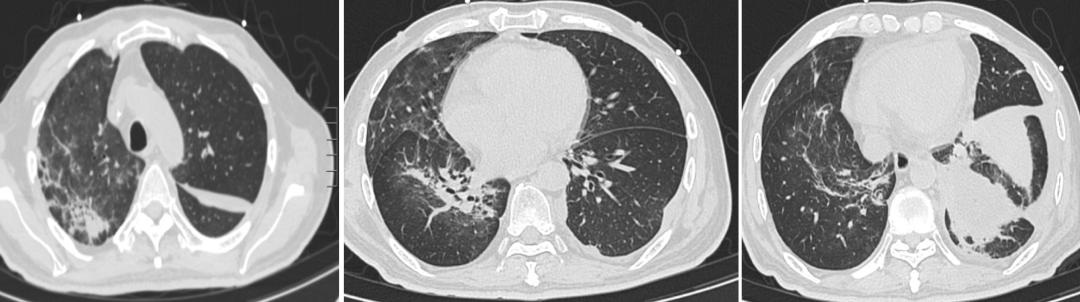

但患者8月29号再次出现发热,最高体温38.2℃,伴干咳和左侧胸闷、胸痛。无腹痛、腹泻等其他不适。体格检查:左下肺叩诊浊音,左肺呼吸音低,左上腹无压痛和反跳痛。SpO2 98-100%, D-二聚体3.950mg/L。复查胸部CT: 两肺散在纤维条影及模糊影,较前好转。左侧胸腔及叶间裂包裹性积液,较前增多。遂行胸腔积液穿刺置管,引流出酱油色胸水150ml 。胸水常规示李凡他试验 + ,细胞计数 2000 10^6/L 偏高, 细胞分类(中性) 90 % , 细胞分类(淋巴) 5 % , 细胞分类(巨噬细胞) 5 %;胸水细菌涂片找到革兰氏阴性杆菌少量。调整抗菌药物:美罗培南 1g 静滴 q8h。经上述治疗后,2020.09.06患者体温正常。

3、第三阶段:出现气胸

2020.09.07患者左侧胸腔引流接袋出现胀气,并引流出少量血性液体,考虑出现出现气胸,予改接水封瓶行闭式引流。可引流出大量气泡。经持续引流一周后,再无气泡溢出。 复方磺胺甲噁唑片及卡泊芬净治疗21天,予以停用。继续美罗培南联合莫西沙星抗感染治疗。

胸部CT:1. 两肺散在炎症,较前相仿;左侧液气胸、叶间裂积气积液。予以左侧胸腔穿刺引流。胸水:棕褐色,细胞计数 775*10^6/L,细胞分类:中性:75%,淋巴:22%,胸水送细菌和真菌检查。

09.13

【图7】治疗过程中出现左侧自发性气胸